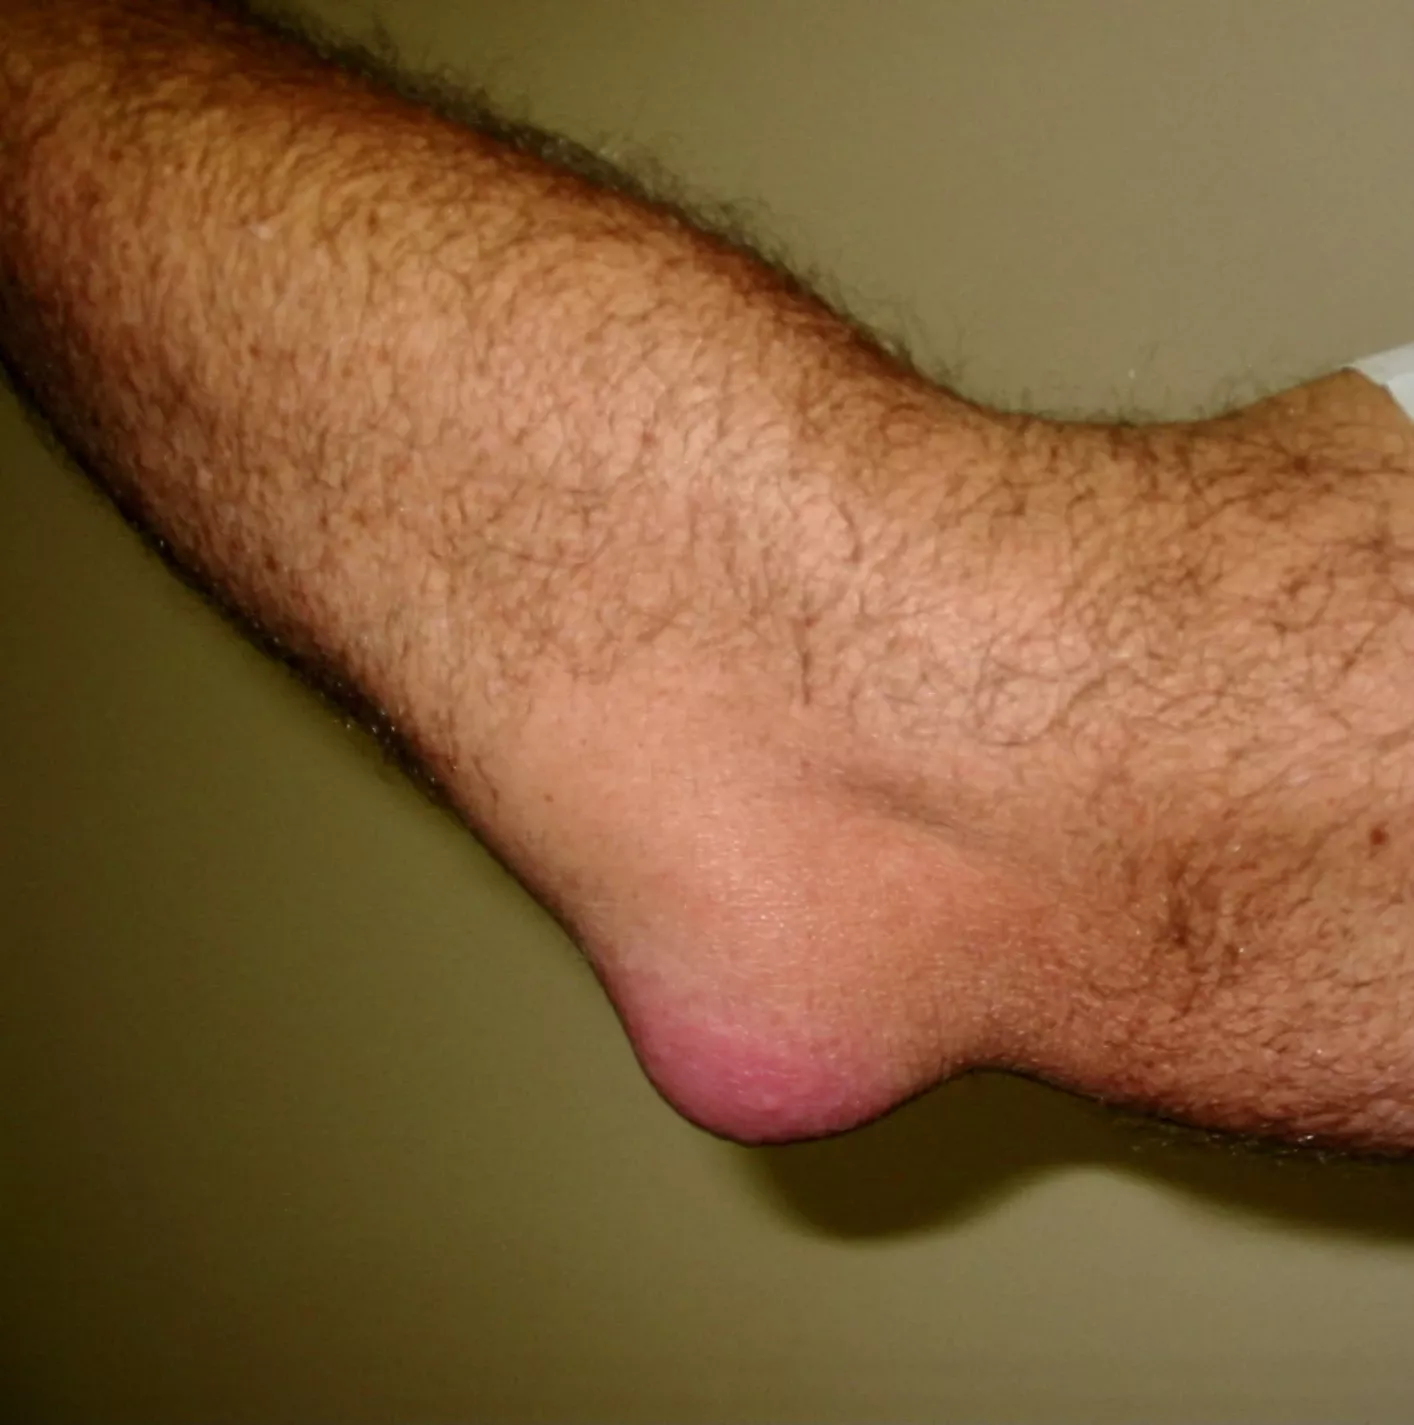

Bursitis olecrani

Omschrijving

Achteraan de elleboog ligt een slijmbeurs die werkt als een kussentje tussen huid en bot. Door druk of wrijving kan deze slijmbeurs irriteren en ontsteken. Soms raakt ze geïnfecteerd.

Klachten

- Zwelling achteraan de elleboog

- Soms roodheid, warmte en pijn

- Koorts of uitbreidende roodheid naar bovenarm/onderarm → meteen arts contacteren

Behandeling

- Rust, ijs en druk op de elleboog vermijden

- Bij infectie: antibiotica en eventueel operatie

- Bij blijvende of ernstige zwelling: operatie om de slijmbeurs te ledigen of te verwijderen

Nazorg

Er wordt een drukverband aangelegd om nabloeding te beperken. Soms tijdelijk gips.